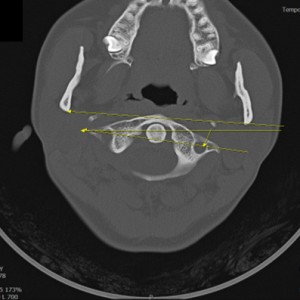

안면 두개골 CT

경추 1,2번의 변위 파악

턱의 소리가 오래되지 않아서 근육의 긴장만 있는 경우 치료 후 소리의 감소가 빠른 편이나 인대의 문제일 경우 턱의 위치를 교정후 인대를 강화하는 치료를 추가적으로 해서 더 줄일수 있습니다. 디스크가 닳아버린 문제라면 치료후에도 소리가 남을수 있습니다. CT와 초음파등의 영상진단을 통해 치료 예후와 경과를 확인 가능합니다.